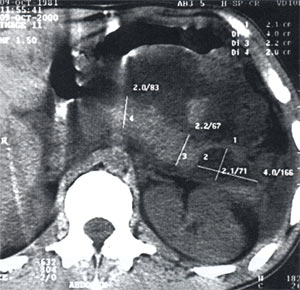

При проведении рентгенографии органов брюшной полости возможно обнаружение тени псевдокисты, а также смещения двенадцатиперстной кишки или желудка. Более информативна ультразвуковая диагностика. УЗИ поджелудочной железы позволяет визуализировать ложную кисту, оценить ее локализацию и размеры, в некоторой степени - связь с протоковой системой, а также наличие или отсутствие осложнений (нагноения, кровоизлияния в полость). В случае сдавления холедоха выявляется расширение желчных протоков, при портальной гипертензии - селезеночной и воротной вен. При малигнизации псевдокисты визуализируются неровные контуры ее стенки.

Для окончательной верификации диагноза, детальной оценки состояния ложной кисты поджелудочной железы и ее содержимого выполняются такие диагностические исследования, как МРТ поджелудочной железы, цитологическое исследование содержимого кисты.